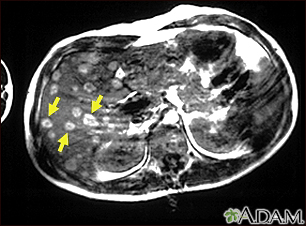

Melanoma of the liver - MRI scanBackMelanoma of the liver - MRI scanThis upper abdominal MRI scan shows multiple tumors in the liver which have spread (metastasized) from a malignant melanoma in an arm or leg. Note the light circular areas throughout the liver (seen mostly on the left side of the screen). E-mail FormEmail ResultsName:Email address:Recipients Name:Recipients address:Message: